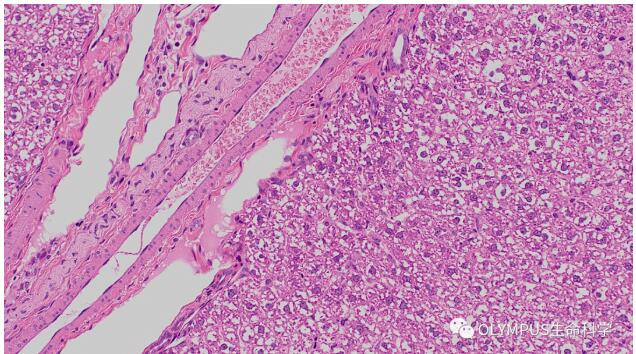

小鼠乳腺

物鏡:UPLXAPO20X

數據出處:中國科學院分子細胞科學卓越創新中心 曾藝組 劉春業